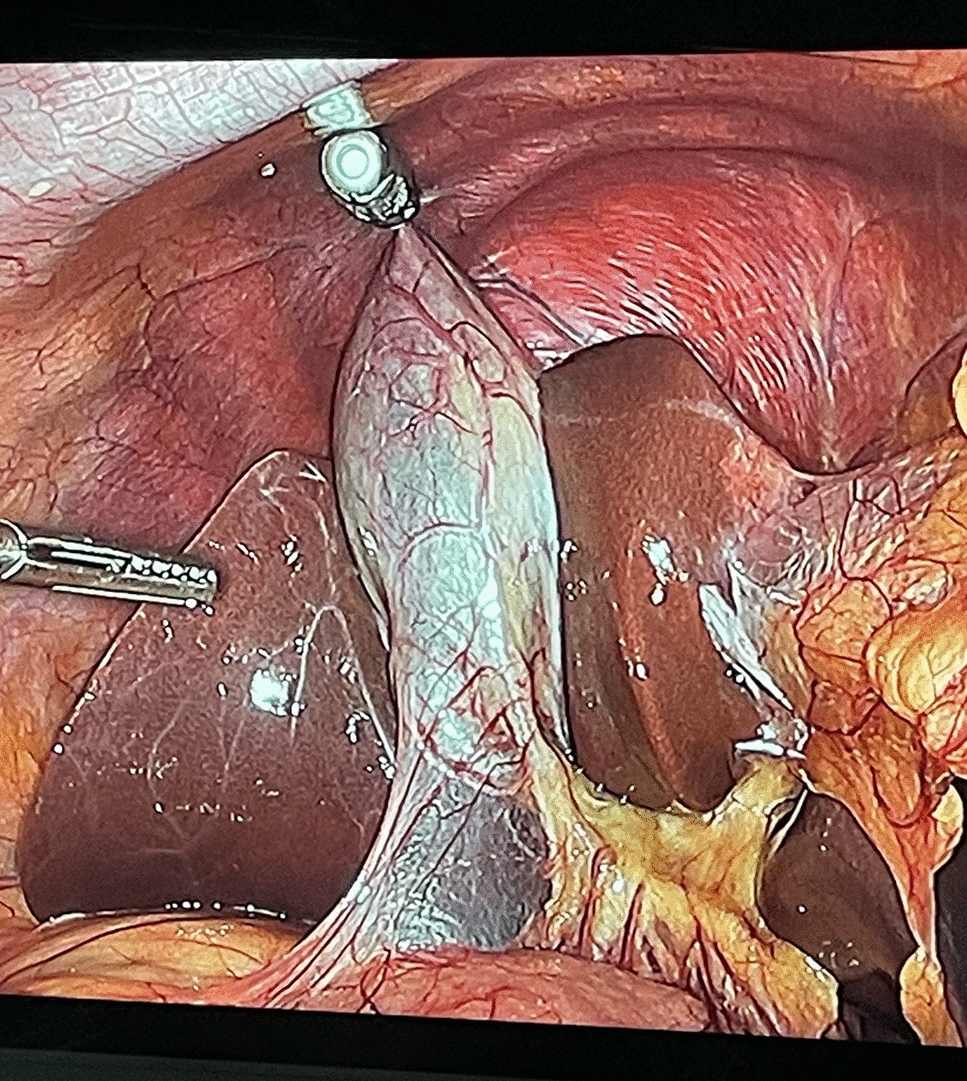

Fig. 3

Operative image of the detachable magnetic grasper attached to the gallbladder (top of image), enabling incisionless retraction with the external robotic arm magnet